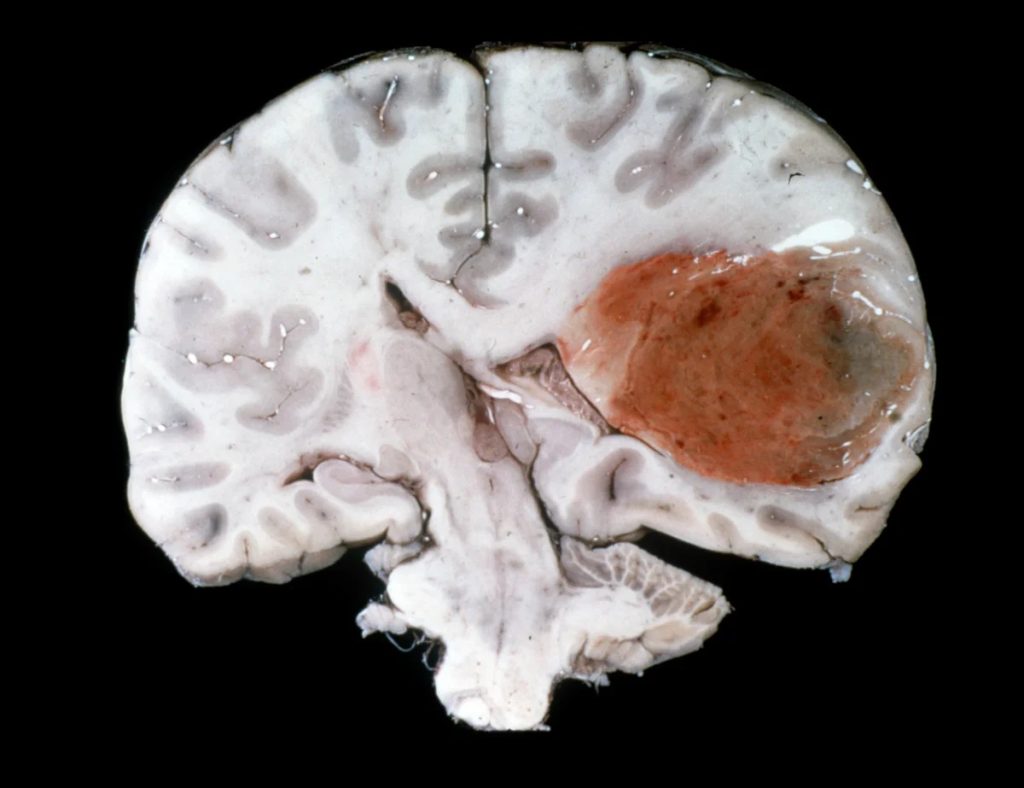

Il glioblastoma rappresenta una sfida medica di grande complessità per la sua aggressività e capacità invasiva nel tessuto cerebrale. Il gruppo di ricerca ha concentrato la sua attenzione su un preciso bersaglio molecolare: i canali emisomici delle connessine. Questi canali, noti per la loro iperattività nei tumori cerebrali, rilasciano molecole come l’ATP e il glutammato che favoriscono la crescita e la diffusione delle cellule tumorali. Sfruttando modelli cellulari derivati da pazienti e modelli murini, i ricercatori hanno testato l’efficacia di un anticorpo denominato abEC1.1, in grado di bloccare selettivamente specifiche connessine (Cx26, Cx30 e Cx32).